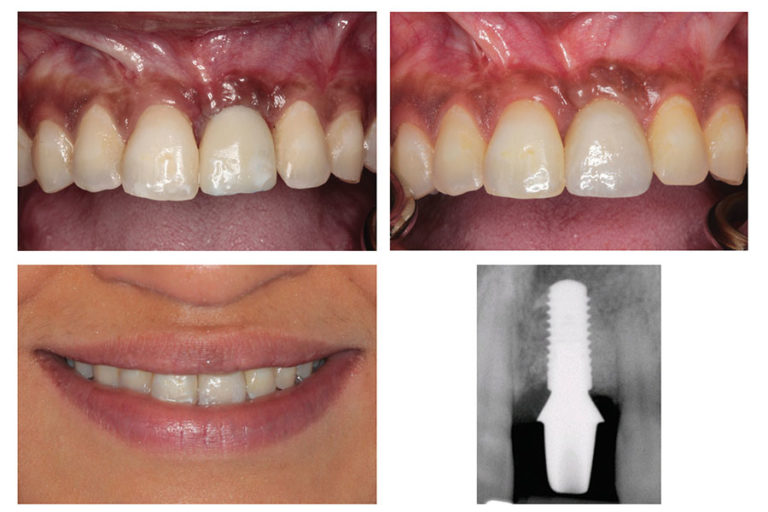

Provisional Implant Crown. in this article we will be presenting a simple technique for fabricating a provisional implant crown with a concave emergence profile. temporary crowns are a way of protecting your gums, implant, or, natural tooth while you are waiting for a permanent cap to be made. They are normally made from a plastic acrylic material or metal, and they should be worn from two to three weeks unless your dentist specifies otherwise. learn everything you need to know about temporary crowns, also known as provisional crowns, which are placed on your teeth while you wait for permanent ones. in this article, he explains why the distinctions between the two types of interim dental restorations are so important by detailing the characteristics and goals of each. learn how to use provisional restorations to enhance diagnostics, esthetics, and patient satisfaction in fixed. Find out the benefits, materials, types, differences, and care tips for these dental restorations. immediate implant placement and provisionalization can be a. Learn when and how dentists use temporary crowns, how long they last, and what to avoid while wearing them. For optimal results the provisional should be placed at the immediate stage of implant surgery and stay in place for 4 months (3). The terms temporaries (or temporary crowns/bridges) and provisionals are often interchanged and thus used incorrectly.

Provisional Implant Crown in this article we will be presenting a simple technique for fabricating a provisional implant crown with a concave emergence profile. learn how to use provisional restorations to enhance diagnostics, esthetics, and patient satisfaction in fixed. in this article we will be presenting a simple technique for fabricating a provisional implant crown with a concave emergence profile. Find out the benefits, materials, types, differences, and care tips for these dental restorations. temporary crowns are a way of protecting your gums, implant, or, natural tooth while you are waiting for a permanent cap to be made. in this article, he explains why the distinctions between the two types of interim dental restorations are so important by detailing the characteristics and goals of each. The terms temporaries (or temporary crowns/bridges) and provisionals are often interchanged and thus used incorrectly. Learn when and how dentists use temporary crowns, how long they last, and what to avoid while wearing them. learn everything you need to know about temporary crowns, also known as provisional crowns, which are placed on your teeth while you wait for permanent ones. immediate implant placement and provisionalization can be a. They are normally made from a plastic acrylic material or metal, and they should be worn from two to three weeks unless your dentist specifies otherwise. For optimal results the provisional should be placed at the immediate stage of implant surgery and stay in place for 4 months (3).